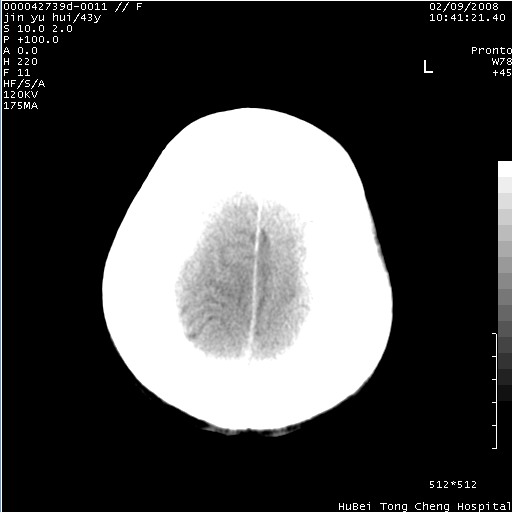

患者 女,43岁。头部外伤26天,经住院治疗,现头痛减轻。申请ct复查,了解颅内情况。

临床诊断:2级脑外伤。

颅脑ct轴位平扫(层厚、层距均为10mm),图像如下: